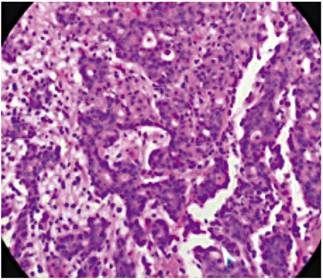

Se planeó realizar una disección submucosa del adenocarcinoma y resección quirúrgica del GIST, pero el paciente presentó un sangrado agudo por ulceración del GIST y fue llevado a gastrectomía subtotal con resección de las dos lesiones. La patología del espécimen quirúrgico mostró un adenocarcinoma moderadamente diferenciado con extensión únicamente a la submucosa superficialmente (Figura 3) y lesión antral de 7 x 7 cm a la cual se le realizó inmunohistoquímica positiva para c-kit (Figura 4), CD 34 positiva y S100 negativo, con un índice mitótico bajo <2 % y un ki 67 <2 % (Figura 5). Todos los ganglios resultaron negativos para lesión. La evolución del paciente es muy satisfactoria actualmente (1 año de seguimiento) y está asintomático; dado que el CG era temprano y que el GIST era de bajo riesgo no necesitó un tratamiento complementario.